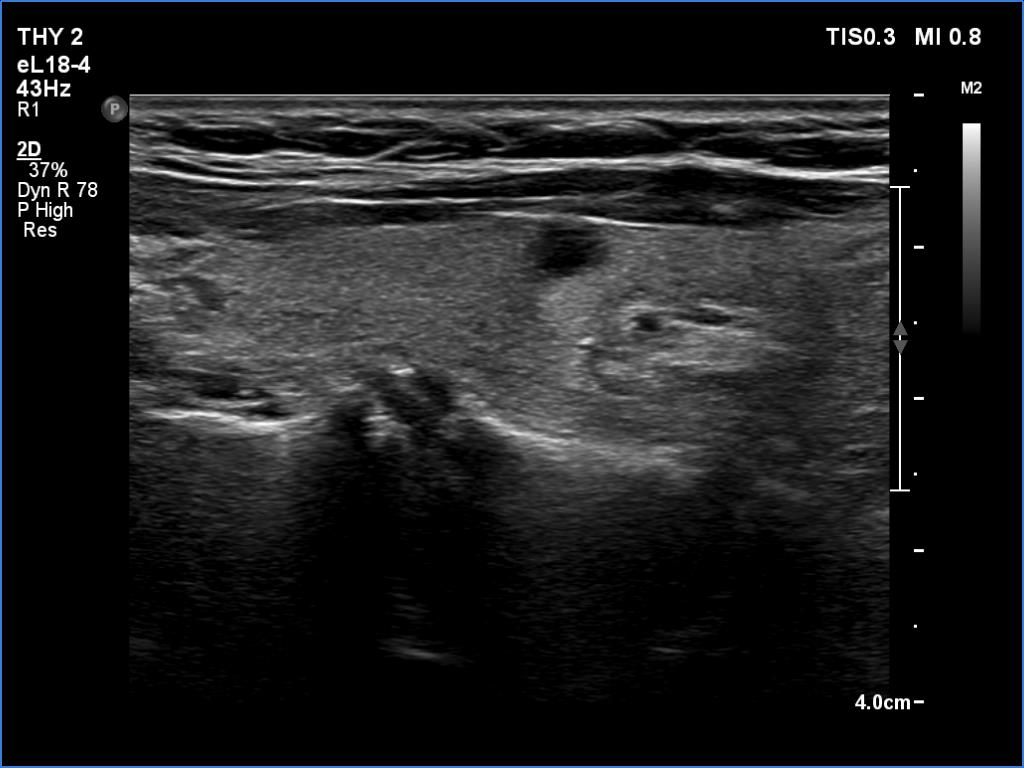

Second examination 6 month later (2nd row of images)

Clinical presentation. The patient was referred for evaluation of hyperparathyroidism. Elevated calcium and parathyroid hormone levels were found during the first evaluation. (These findings were not yet available when I first examined the patient.) Further evaluation disclosed a hyperfunctioning right lower parathyroid. The patient was operated on but no parathyroid tissue was found on histopathology. (A more experienced parathyroid surgeon was quarantined at the scheduled time of the operation, so a less experienced colleague performed the surgery.) Both hypercalcemia and hyperparathyroidism have persisted.

Ultrasonography revealed a hypoechoic mass corresponding to the right lower parathyroid.

If we compare the first and second ultrasound examination, it is evident that the ultrasound examination was not performed according to the rules of the profession at the first visit. (I will just mention that although in this case we only videotaped part of the entire study, we obviously overlooked the parathyroid gland under the right lobe. The reason for this is that we did not examine the part below the thyroid in the transverse section, and in the longitudinal section we started to examine the lower part of the thyroid too medially.)